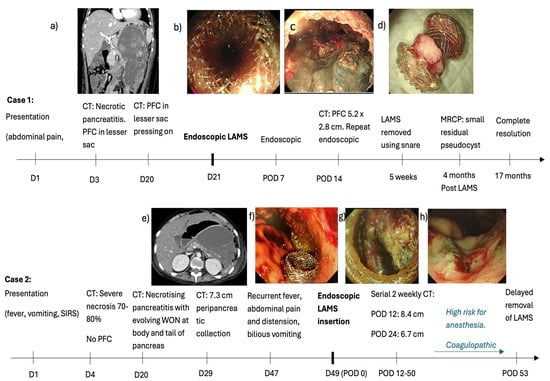

(1) A 10-year-old boy presented with a 1-day history of abdominal pain, vomiting and fever (37.7 Celsius). Amylase and lipase were elevated to more than 3 times normal (863 U/L and 969 U/L, respectively). A computerised tomography (CT) scan on day 3 revealed an oedematous pancreas with PFC in the lesser sac (6.6 × 6.0 cm). Oral feeds could be commenced and progressed to a full diet by day 16 of admission. Vomiting recurred together with high-spiking fevers by day 18. A CT scan on day 20 revealed preserved homogenous enhancement of the pancreas and a large PFC (10.7 × 9.9 × 19.1 cm) with internal debris and well-defined walls that were abutting the stomach, causing a significant mass effect (Figure 1a). On day 21, under general anaesthesia, an endoscopic ultrasound (EUS)-guided cysto-gastrostomy was performed and a Boston Hot AXIOS LAMS (10 length × 15 mm diameter) was inserted (Figure 1b). Endoscopy was repeated one week later to perform a necrosectomy (using a grasper, Roth net, and snare) and lavage using hydrogen peroxide. A CT scan at 2 weeks after LAMS insertion revealed a reduction in the size of the PFC to 5.2 × 2.8 cm. Necrosectomy was repeated for persistent PFC on day 14 after the initial insertion of the LAMS (Figure 1c). Antibiotics were tailored to the results of the culture of the necrotic tissue obtained at endoscopy. His fevers settled, and his general condition improved with the re-commencement and establishment of full feeds by week 5 of admission. The LAMS was removed endoscopically using a snare at 5 weeks after insertion (Figure 1d). He was discharged well at 2 months after admission. Magnetic resonance cholangiopancreatography 4 months after discharge showed no pancreatic duct disruption or any pancreatic or bile duct anomaly. He remains well at 24 months with complete resolution of the PFC on follow-up ultrasound scans.

Figure 1.

Clinical course of two cases of acute pancreatitis with pancreatic fluid collections (PFCs). (a) Day 20 CT scan showing a large PFC abutting the stomach, causing a significant mass effect (b) Endoscopic ultrasound (EUS)-guided cysto-gastrostomy on Day 21 using a Boston Hot AXIOS LAMS (10 length × 15 mm diameter). (c) Necrosectomy repeated 14 days later (d) LAMS removed at 5 weeks (e) CT scan shows an enlarging PFC causing compression and anterior displacement of stomach. (f) LAMS deployed on day 49 of illness. (g) Endoscopic necrosectomy performed for persistent WON 50 days after LAMS insertion. (h) Patent healthy cystogastrostomy tract after removal of LAMS..

(2) A 17-year-old boy with relapsed pre-B cell acute lymphocytic leukaemia and Klinefelter syndrome presented with fever, nausea, and vomiting 13 days after receiving Peg-asparaginase. Amylase (890 U/L) and lipase (2084 U/L) were elevated to more than 3 times the upper limit of normal. A CT scan revealed acute pancreatitis with no obvious necrosis or PFC. This progressed to severe necrosis of 70–80% of the pancreatic parenchyma on day 4. There was no significant PFC. CT scan on day 20 for new-onset fever (>38 C) revealed necrotising pancreatitis with evolving WON in the body and tail of the pancreas. He developed thrombocytopenia in addition to his deranged INR, resulting in a spontaneous retroperitoneal hematoma on day 29. The CT scan, which was performed for the retroperitoneal haematoma, revealed similar appearances of the pancreas. He developed bilious vomiting with abdominal pain and distension by day 47. A CT scan revealed an enlarging PFC (12.2 cm from 7.3 cm), resulting in compression and anterior displacement of the stomach (Figure 1e). There was internal debris suggestive of WON. On day 49, under general anaesthesia, he underwent EUS and endoscopic cyst-gastrostomy with deployment of LAMS like case 1 as above. (Figure 1f) The aspirated cyst fluid was rich in amylase (1724 U/L vs. serum amylase 31 U/L), and cyst fluid culture yielded Stenotrophomonas and Actinomyces. He developed pancreatic endocrine and exocrine insufficiency requiring long-term insulin for hyperglycemia and transient octreotide for loose stools, respectively. He developed other co-morbidities such as mycobacterium tuberculosis pneumonia requiring a 4-drug anti-tuberculosis regimen, cytomegalovirus viraemia requiring ganciclovir, left iliac vein thrombosis, hypertension due to chronic steroid use, and BK virus haemorrhagic cystitis, which responded to ciprofloxacin and herpes simplex keratitis in his right eye. Further endoscopy for necrosectomy could not be performed because of his poor general condition, high risk for anaesthesia, and coagulopathy. The LAMS was left in situ with surveillance CT scans, which revealed a progressive decrease in maximum WON size from 12.2 cm to 6.7 cm and 6.2 cm on days 63, 75, and 93 of illness and days 12, 24, and 50 of the LAMS, respectively. In view of the improving and stable general condition with persistent residual WON, endoscopic necrosectomy was performed as per case 1 on day 93 of illness and day 50 of LAMS insertion (Figure 1g). The necrosectomy seemed complete with healthy tissue within the cavity. Hence, the LAMS was removed using a snare. At the end of the procedure, a patent healthy cystogastrostomy tract could be visualised (Figure 1h). A CT scan on the day after the LAMS removal revealed no debris and a small residual PFC. Our plan was to monitor progression with surveillance scans. Unfortunately, the family decided to bring the boy back home overseas, where he succumbed after 3 weeks despite continued management.